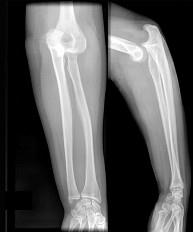

问题 图示脱位的治疗 ( )

选项 A、手法复位,石膏托90°固定6周 B、手法复位次日即开始局部按摩治疗 C、手法复位,肘部绷带包扎,随意活动 D、手法复位,石膏托90°固定3周 E、均应手术

答案 D